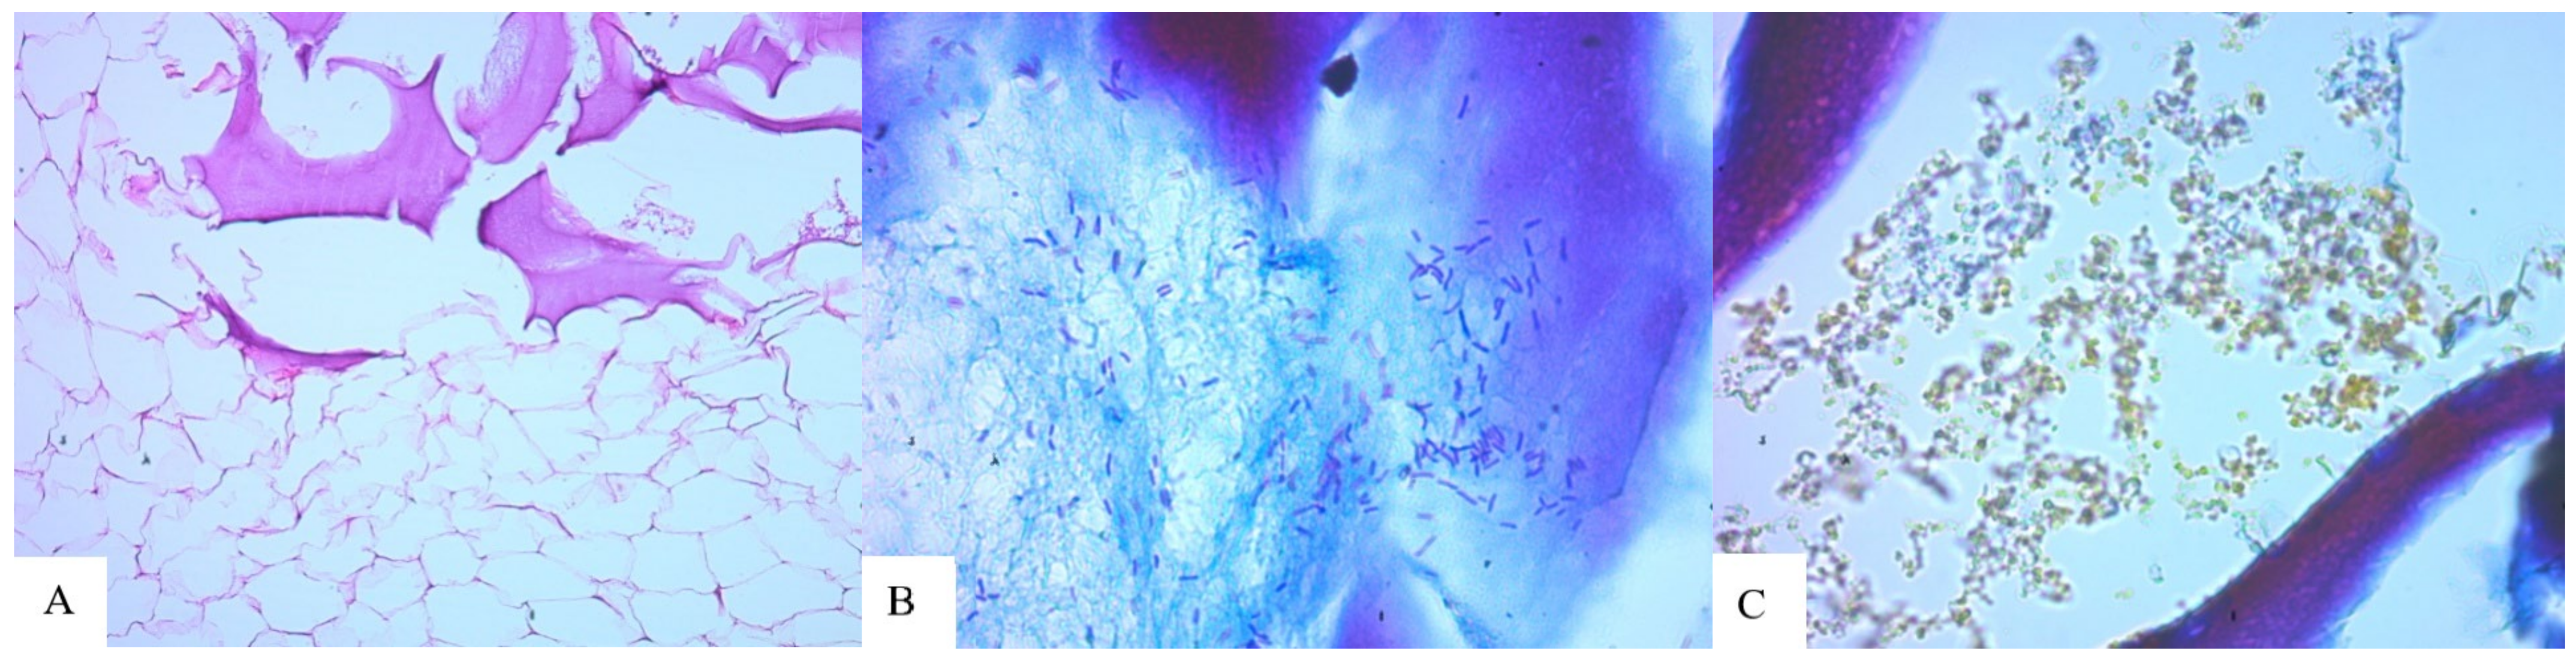

- Foreign substance (gel) migrated in the tissues, provoking the active growth of connective tissue;

- Aseptic and septic inflammatory reactions;

- Sections of round-shaped petrifications with clear contours;

- Lymphoid cell reaction, the presence of voids and necrotic masses, and the formation of cystic cavities;

- Pronounced deformation of adipocytes;

- Muscle tissue with extensive necrosis and effusion of the protein component;

- Numerous mast cells;

- Isolated, giant Pirogov–Langhans cells surrounded by lymphocytes and macrophages.